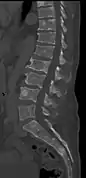

The diagnostic examination of a person with suspected multiple myeloma typically includes a skeletal survey. This is a series of X-rays of the skull, axial skeleton, and proximal long bones. Myeloma activity sometimes appears as "lytic lesions" (with local disappearance of normal bone due to resorption) or as "punched-out lesions" on the skull X-ray ("raindrop skull"). Lesions may also be sclerotic, which is seen as radiodense.[70] Overall, the radiodensity of myeloma is between −30 and 120 Hounsfield units (HU).[71] Magnetic resonance imaging is more sensitive than simple X-rays in the detection of lytic lesions, and may supersede a skeletal survey, especially when vertebral disease is suspected. Occasionally, a CT scan is performed to measure the size of soft-tissue plasmacytomas. Nuclear Medicine Bone scans are typically not of any additional value in the workup of people with myeloma (no new bone formation; lytic lesions not well visualized on nuclear bone scan).

- Pathological fracture of the lumbar spine due to multiple myeloma

- CT scan of the lower vertebral column in a man with multiple myeloma, showing multiple osteoblastic lesions: These are more radiodense (brighter in this image) than the surrounding cancellous bone, in contrast to osteolytic lesions, which are less radiodense.